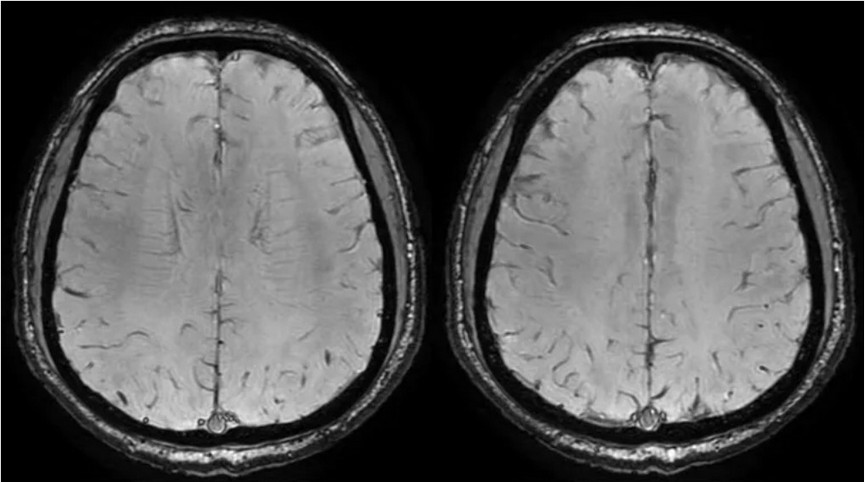

临床申请:颅脑平扫,静脉成像,磁敏感成像,颅内静脉血管黑血成像。

图像不逐一罗列,未见异常。

SWAN未见异常。

PC-MRV未见异常。

颅内静脉黑血成像,CUBE T1fs w/o +c,静脉窦未见异常。